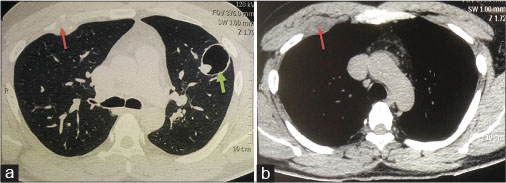

His history also included his presentation with repeated increased frequency of stool 3–4/day, semisolid without blood or mucus in December 2006. 68Ga-labelled [1,4,7,10-tetraazacyclododecane-1,4,7,10tetraacetic acid]-1-Nal3-octreotide (68Ga-DOTA-NOC) positron-emission tomography (PET) suggested enhancing pancreatic head (HOP) mass with central necrosis which was non-fluoro deoxycolic glucose (FDG) avid on PET-computed tomography. With the suspicion NET, the patient was advised surgery, but he denied any intervention.

The HOP mass (8.3 cm × 6.2 cm × 6.2 cm) was more 68Ga-DOTA-NOC avid while the D1–D2 mass (2.4 cm × 2.9 cm) was more FDG avid [Figure 2].

| Figure. 2 Axial fluoro deoxycolic glucose positron-emission tomography and (1,4,7,10-tetraazacyclododecane-1,4,7,10-tetraacetic acid)-1-Nal3-octreotide positron-emission tomography image of the upper abdomen reveal large soft tissue intensely (1,4,7,10-tetraazacyclododecane-1,4,7,10-tetraacetic acid)-1-Nal3-octreotide avid and fluoro deoxycolic glucose positron-emission tomography nonavid mass in the head and uncinate process of pancreas (white arrows in image a, b, and c) and another polypoidal intraluminal fluoro deoxycolic glucose positron-emission tomography avid and (1,4,7,10-tetraazacyclododecane-1,4,7,10-tetraacetic acid)-1-Nal3-octreotide nonavid mass in D2 part of duodenum (dashed white arrows in image a, b, and c)